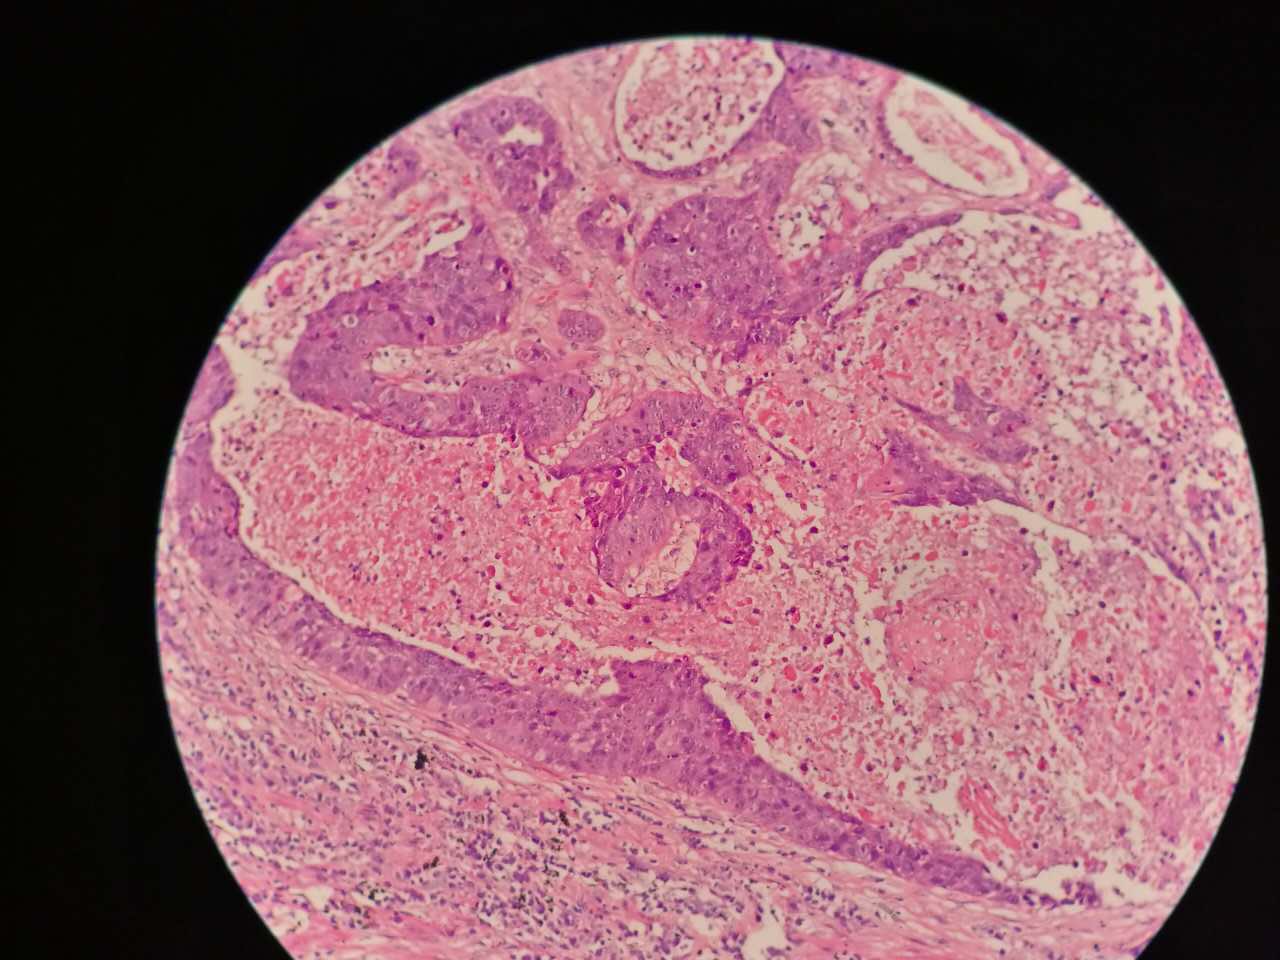

这个鳞癌不是早期

坏死也可以很大

较大的粉红区都是坏死,可以看出坏死是因为巢团大,中央坏死

下图是放大

巢团可以很大,中央血供不足,就会坏死

中央红色的,有碎核